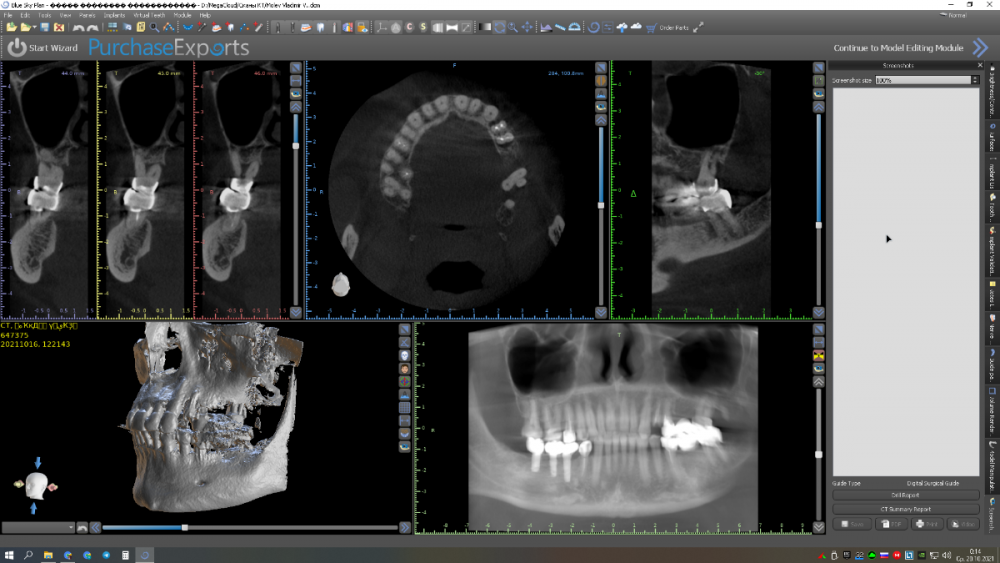

Женька Опубликовано 19 октября, 2021 Автор Поделиться Опубликовано 19 октября, 2021 @annda что-то покрутил я КТ и озадачился. С 2.7 то проблемы пожалуй посерьёзнее будут И самое интересное, что сразу что-то туда я не поставлю Может мост 2.4-2.5-2.6 и консоль 2.7 нормальный вариант? Или не торопиться, убрать 2.7 и подождать,а потом синус-шминус имплантация и нормальная ортопедия? Ссылка на комментарий

Raystom Опубликовано 19 октября, 2021 Поделиться Опубликовано 19 октября, 2021 Не мой кейс, но подскажите, пожалуйста, насколько критично в данном случае будет отсутствие 37 и 27? Если я правильно понимаю, то мост 35-37 несостоятелен и 37 в итоге на удаление. Так нельзя ли сделать имплантацию 24-26, потом мост и позже снять коронки снизу и установить имплант-коронку 36 и коронку 35? Ссылка на комментарий

annda Опубликовано 20 октября, 2021 Поделиться Опубликовано 20 октября, 2021 Не думаю, что чел радостно побежит удалять два моста и ставить пять имплантатов вместо одного.. Сказать ему, конечно , об этом нужно. И сказать, что чем больше он созревает эту проблему, тем дольше и дороже он потом ее будет решать . И обязательно взять сегодня отказ от ее решения сегодня. Уж как вы потом эти пазлы будете складывать, дело десятое. Но по сути, лучше, чтобы верхняя зубная дуга была чуть длиннее , чем нижняя, хотя бы на полкоронки, язык не травмируется. 1 1 Ссылка на комментарий

annda Опубликовано 3 ноября, 2021 Поделиться Опубликовано 3 ноября, 2021 (изменено) Желательно планировать, чтобы коронка верхнего моляра была дистальнее нижней коронки. Щеки могут прикусывать. Хотя, и на своих зубах тут конкретно верхний ряд короче слева, может и обойдется. Изменено 3 ноября, 2021 пользователем annda Ссылка на комментарий

Женька Опубликовано 3 ноября, 2021 Автор Поделиться Опубликовано 3 ноября, 2021 @annda может тогда в бугор дистальный поставить? Но с ортопедией возникнут вопросы тогда... В дистобукальный корень некуда... карман,все дела. А как на снимках хоть в трифуркации можно торкнуть Ссылка на комментарий

annda Опубликовано 3 ноября, 2021 Поделиться Опубликовано 3 ноября, 2021 Не парьтесь, у нее и сейчас короче свой свой верхний зубной ряд. Ссылка на комментарий